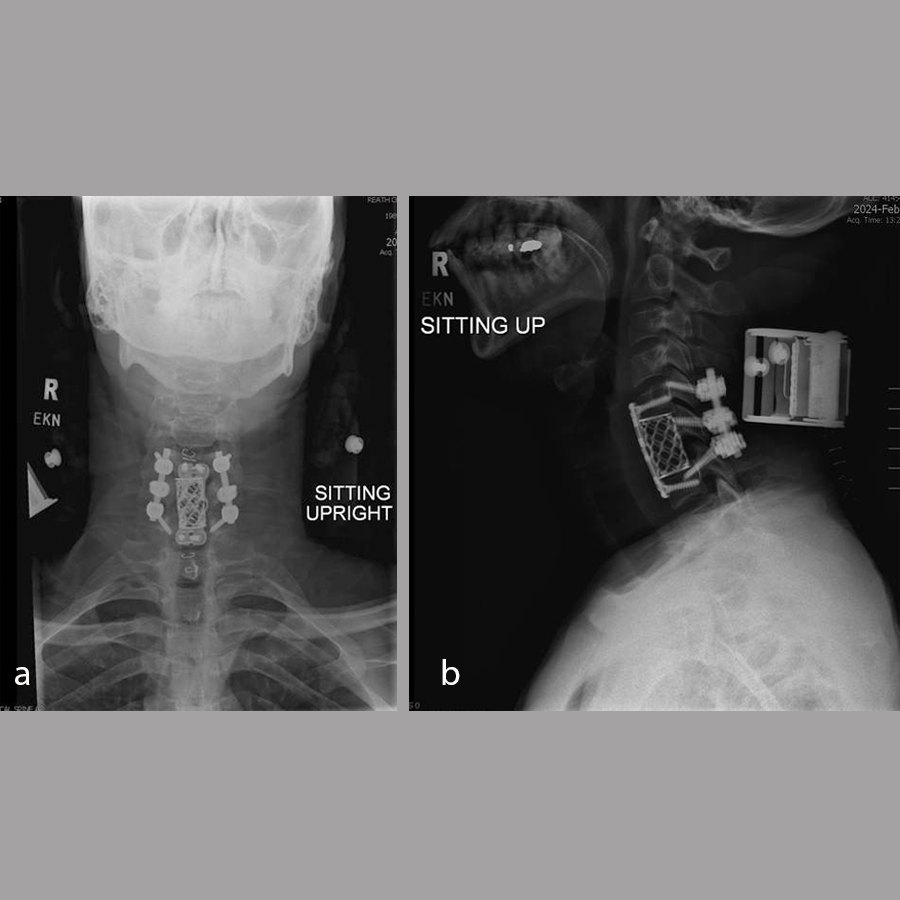

A diagnosis was made of cervical spinal stenosis largely attributable to stenosis at C4/5, with lesser stenosis at C5/6 and cord compression causing sub-acute central cord syndrome. Anterior decompression was recommended to alleviate symptoms, and C4/5 anterior cervical discectomy and fusion (ACDF) was performed on March 7, 2024. Fig 9 shows postoperative imaging.

Anteroposterior and lateral, flexion, and extension x-rays showed that the graft at C4/5 appeared to be in the original position as expected. There was no evidence of loosening of the screw-plate construct. Some bridging fusion was present between the superior C5 endplate of the graft. There continued to be incomplete consolidation between C4 and the graft but no motion of the graft itself. Flexion/extension films did not show any instability.